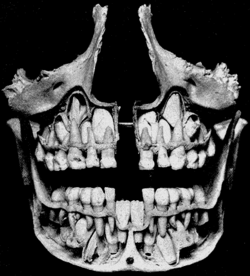

This cut view of a child's skull shows permanent teeth located above and below the deciduous teeth prior to exfoliation. The deciduous mandibular central incisors have already been exfoliated (Gray's Anatomy) | |

Deciduous teeth are now more commonly known as primary teeth. They are also known as baby teeth, temporary teeth and milk teeth.[1] They are the first set of teeth in the growth development of humans and other diphyodont mammals. They develop during the embryonic stage of development and erupt—that is, they become visible in the mouth—during infancy. They are usually lost and replaced by permanent teeth, but in the absence of permanent replacements, they can remain functional for many years.

The primary dentition is made up of central incisors, lateral incisors, canines, first molars, and secondary molars; there is one in each quadrant, making a total of four of each tooth. All of these are gradually replaced with a permanent counterpart except for the primary first and second molars; they are replaced by premolars. There are a number of different Dental notation systems including the ISO System (WHO and FDI endorsed and most widely used system), Palmer Notation and the Universal Tooth Designation System by the capital letters A through T.[1] In other parts of the world, the FDI notation system The replacement of primary teeth begins around age six, when the permanent teeth start to appear in the mouth, resulting in mixed dentition. The erupting permanent teeth cause root resorption, where the permanent teeth push on the roots of the primary teeth, causing the roots to be dissolved by odontoclasts (as well as surrounding alveolar bone by osteoclasts) and become absorbed by the forming permanent teeth. The process of shedding primary teeth and their replacement by permanent teeth is called exfoliation. This may last from age six to age twelve. By age twelve there usually are only permanent teeth remaining.